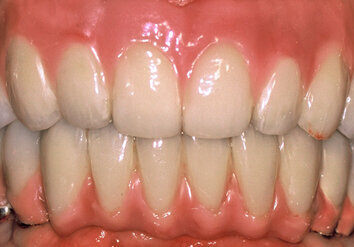

Two months later, full mouth rehabilitation of the maxilla (supported by six implants) and mandible (supported by six implants) was completed by fabrication of RIRDs using telescopic crowns as attachments, as previously described.7-9 Customized abutments served as primary telescopes and electroformed pure gold copings (0.25 mm thickness, AGC Galvanogold, Au>99.9%, Wieland Dental Systems Inc., Pforzheim, Germany) served as secondary telescopes (Fig. 9, Fig. 10). The metal frameworks was milled from titanium (Zenotec Ti, Wieland Dental Systems Inc., Pforzheim, Germany; Fig. 11) and veneered using a photocured indirect ceramic polymer (Ceramage, Shofu, Ratingen, Germany; Fig. 12 – Fig. 15).

Fig. 12. Final RIRD using telescopic crowns as attachment (front view).